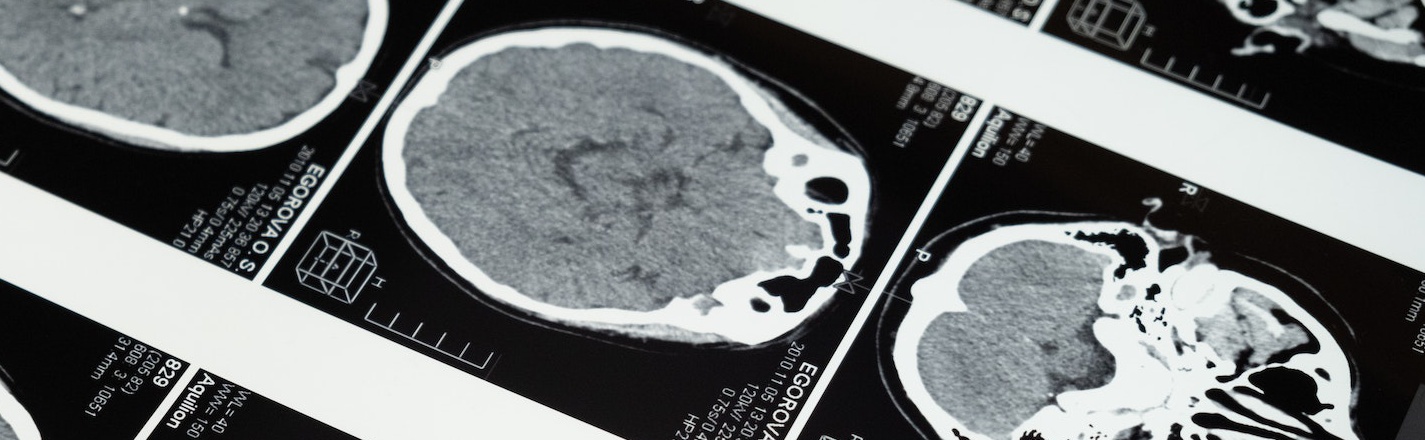

Study identifies brain areas altered during hypnotic trances

“By scanning the brains of subjects while they were hypnotized, researchers at the School of Medicine were able to see the neural changes associated with hypnosis”.